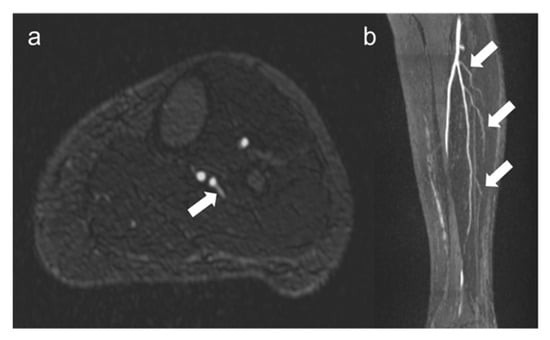

Fibular perforators were found in 87% of 100 legs (46 right legs and 41 left legs). Image examples of fibular perforators are presented in Figure 4.

Figure 4.

Visualization of fibular perforators using QISS-MRA. In panel (a), the exit of a fibular perforator is seen in transverse view (white arrow). In panel (b), three fibular perforators can be seen in sagittal view (white arrows). The images belong to two different patients.

The median number of perforators varied within patients (2 [1, 3]) and also between the right and left legs (2 [1, 3] vs. 3 [1, 3], p = 0.24). There were no significant differences between the two observers concerning the determination of perforators (Table 3).